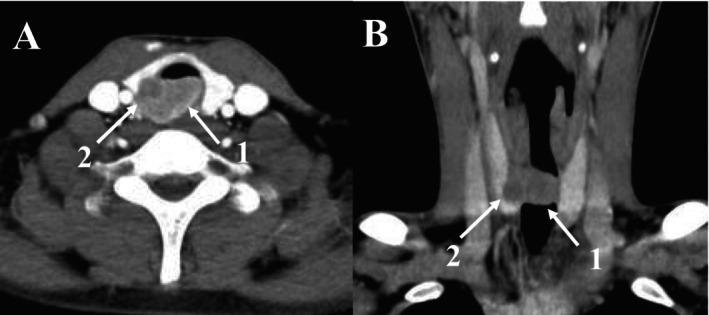

A Tracheal Perivascular Epithelioid Cell Tumor in a 17-Year-Old Male.

This case is the second to report a patient with a tracheal perivascular epithelioid cell tumor (PEComa), who previously underwent multiple intratracheal CO cryotherapy treatments. Standardized surgical resection and postoperative scar management resulted in a favorable prognosis after 4 years of follow-up, highlighting the critical role of surgical intervention in rare primary tracheal tumors.